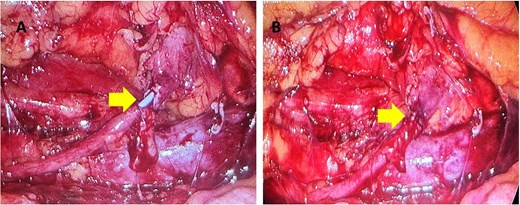

Initial work-up revealed microscopic haematuria and a mildly elevated creatinine of 156 μmol/L (65.4–119.3 μmol/L). A computerized tomogram (CT) urogram showed proximal hydroureteronephrosis with preserved renal cortex (Fig. 1). A diethylenetriamine pentaacetate (DTPA) renogram with diuretic showed accumulation of contrast then prompt excretion with administration of diuretic, suggesting partial obstruction or hypotonic collecting system (Fig. 2). At this point alternative diagnoses were considered, including RU. Ongoing severe right flank pain was noted despite multimodal analgesia and a right-sided nephrostomy was placed with immediate relief of pain and obstruction. Figure 3 shows the nephrostogram with S-shaped hydroureter. No further analgesia was required, and creatinine normalized (90 μmol/L). The case was discussed at a multidisciplinary meeting, wherein a unanimous diagnosis of RU was confirmed, and a plan for minimally invasive laparoscopic dissection and re-anastomosis of the ureter was made.

Interventional image during nephrostomy placement demonstrating S-shaped ureter and clear point of obstruction.